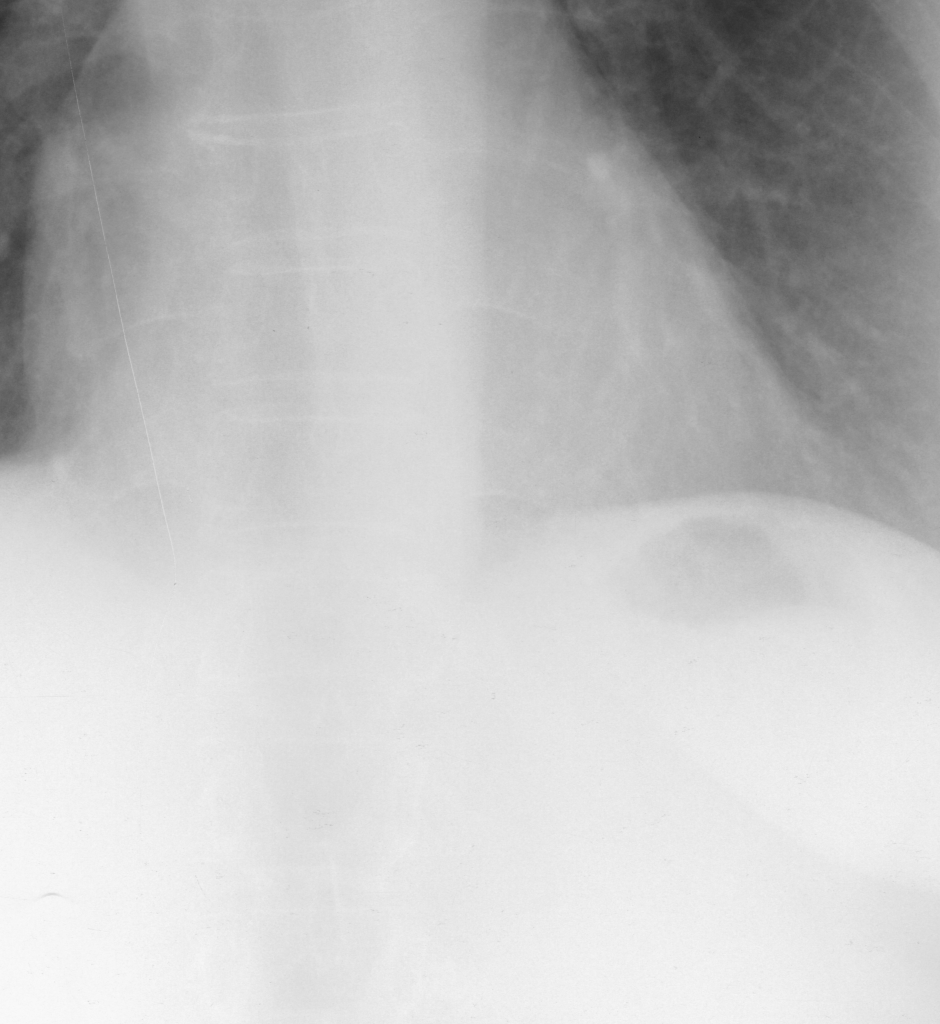

Fig. 3 shows image samples from the above datasets.

Figure 3: Image diversity across four datasets: (a) JSRT, (b) Montgomery County X-ray, (c) NIH ChestX-ray14, and (d) CheXpert

4.2 Training XVertNet

We developed a patch-wise U-Net-based architecture that processes two 512×512512\times 512-pixel regions of interest (ROIs) for each image; one centered on the upper spinal cord and another on the lower spinal cord. As shown in Fig. 3, our datasets exhibit diverse spatial characteristics, with images varying in dimensions (e.g., 2048×20482048\times 2048, 4020×48924020\times 4892, and 1024×10241024\times 1024 pixels) and bit depths (8-bit and 12-bit). This variability in image features poses a significant challenge for creating a robust enhancement model.